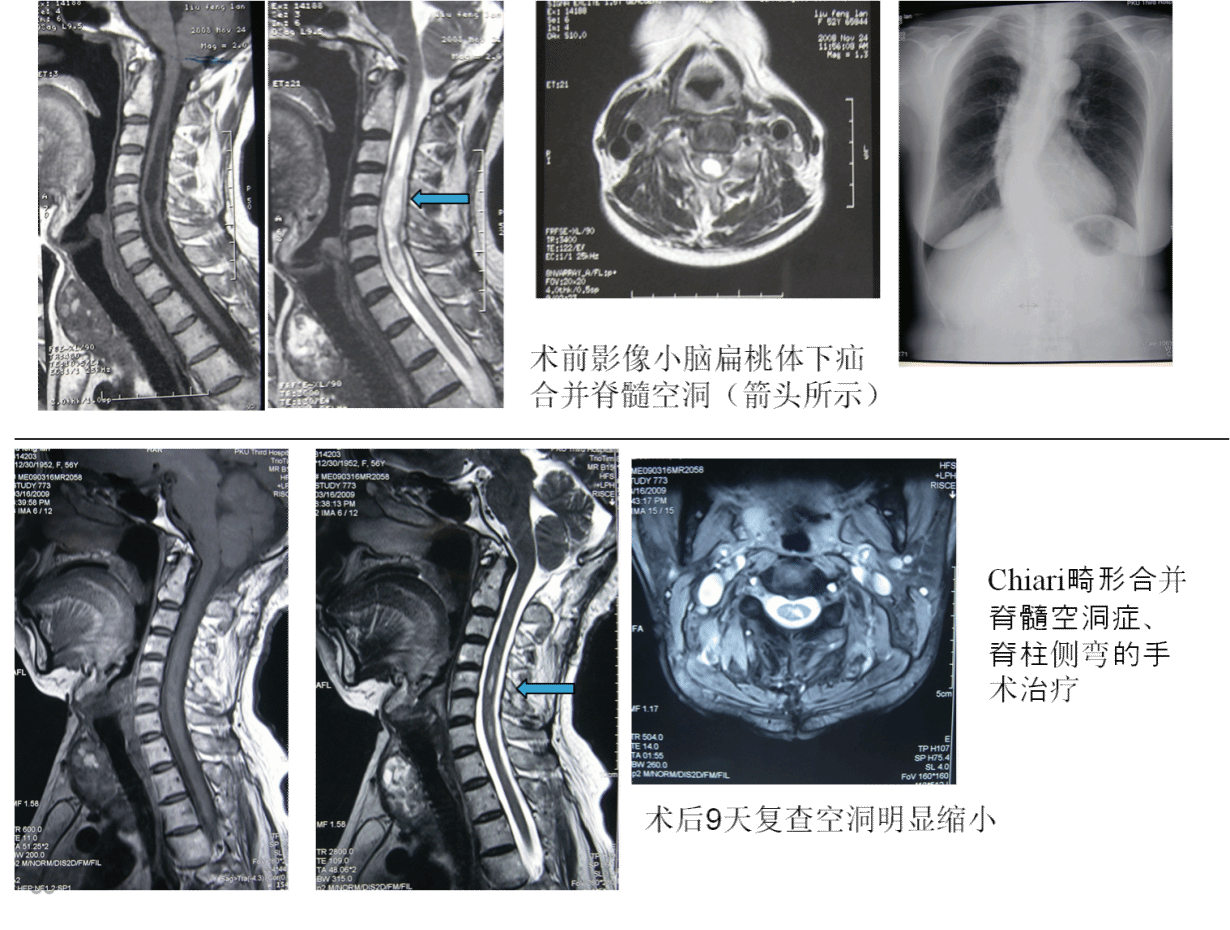

个体有差异,大部患者术后3月内会明显改善,但也有患者术后3-4年才会改善,所以需要长期随诊。下图就是脊髓空洞合并小脑扁桃体下疝(Chiari畸形)手术前后的影像学表现: